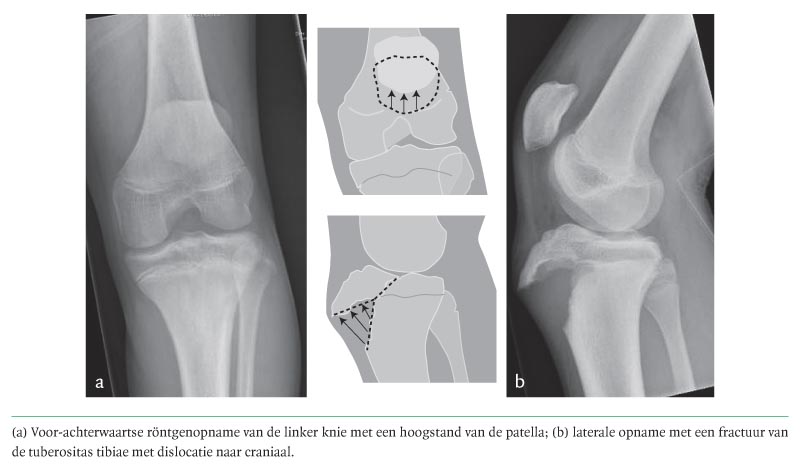

Op onze afdeling Spoedeisende Hulp zagen wij een 15-jarige jongeman met een pijnlijke linker knie. De klacht was ontstaan nadat patiënt overeind was gesprongen. De voorgeschiedenis vermeldde een patellaluxatie links. Bij onderzoek was de linker knie gezwollen; flexie en extensie waren beperkt en pijnlijk. Het was niet mogelijk het been gestrekt te heffen. De röntgenfoto in voor-achterwaartse richting liet behalve een hoogstand van de patella geen afwijkingen zien (figuur a). Op de laterale opname was een fractuur van de tuberositas tibiae zichtbaar met dislocatie naar craniaal (zie figuur b), waarbij de fractuurlijn gedeeltelijk door de groeischijf…